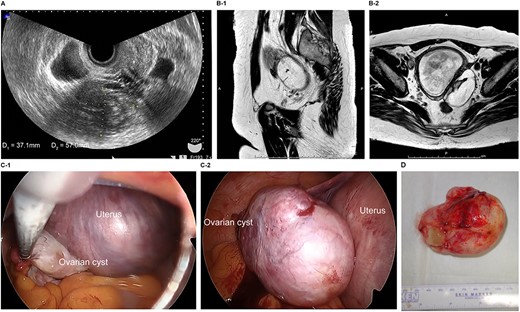

The patient was a 29-year-old, gravida 1, para 0 woman with no familial or medical history. She conceived naturally and was diagnosed a left ovarian cyst at 7 weeks of gestation by another doctor. She was referred to our hospital for further examination and operation. TVUS revealed a fetus in the uterus and a mass 7 cm in diameter on the left ovary, which appeared to be a dermoid cyst. MRI revealed left ovarian cystic tumors with fat tissue. The laboratory values, including levels of tumor markers (e.g. CEA, CA-125, CA 19-9 and SCC) were within the normal limits. We performed single-port laparoscopic surgery at 15 weeks and 3 days gestation to remove the left ovarian cysts. The procedure was performed within 99 minutes, and there were no complications (Fig. 3).

Imaging studies and laparoscopic views and specimen photograph of case 3. (A) Transvaginal ultrasound image showing an ovarian cyst. (B-1) Sagittal T2-weighted MRI showing an ovarian cyst. (B-2) Axial T2-weighted MRI showing an ovarian cyst. (C-1) Gestational uterus: ovarian cyst was moved from the pouch of Douglas. (C-2) Ovarian cyst was moved and located on the gestational uterus. (D) Ovarian Cyst.